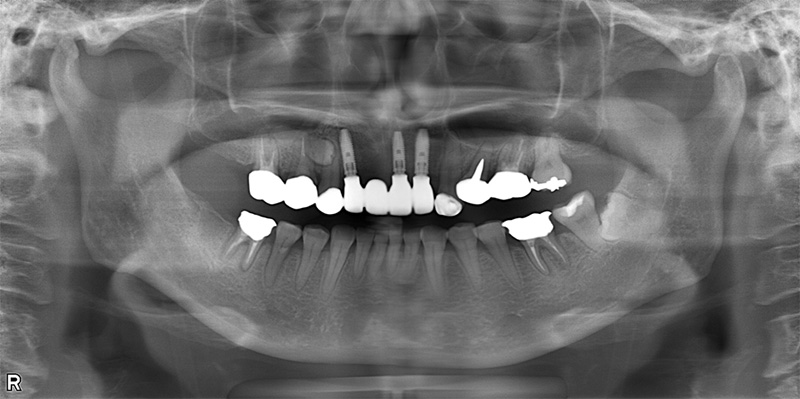

57歳男性

治療前

治療後

| 施術名 | インプラント治療 |

| 施術の説明 | インプラント治療とは、歯を抜いた所にチタン製の人工歯根を埋入し、新しく歯を入れる方法です。 |

| 施術の副作用 (リスク) | 腫れや疼痛を感じる、違和感を感じるなどの症状を生じることがあります。 |

| 施術の価格 | 53万円~+消費税 |